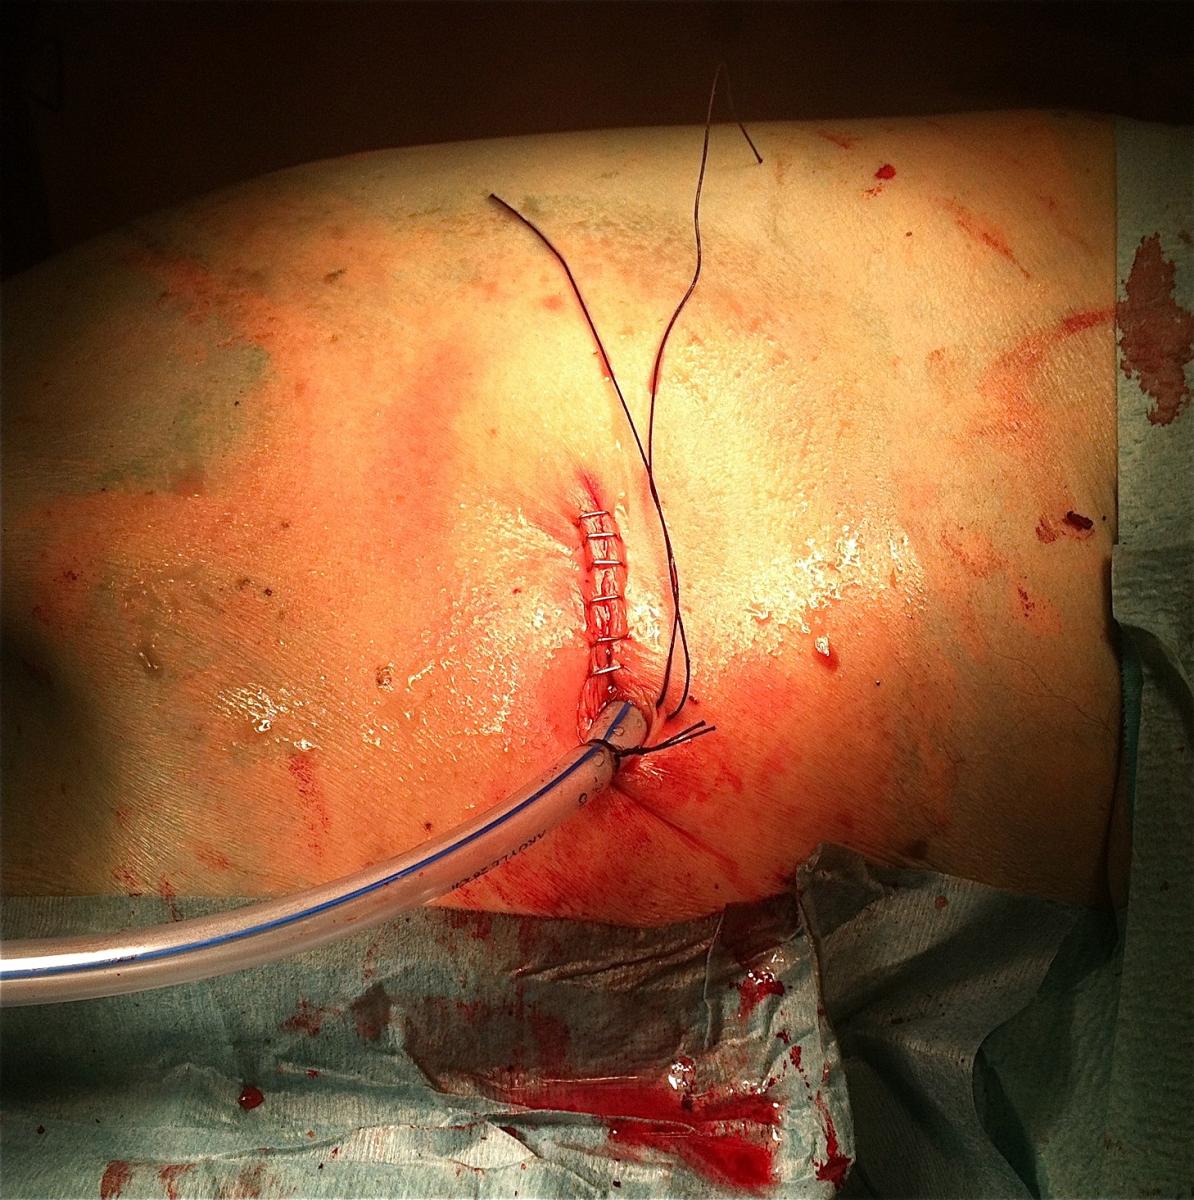

Image 3: External aspect of the incision with the chest tube (28Fr)